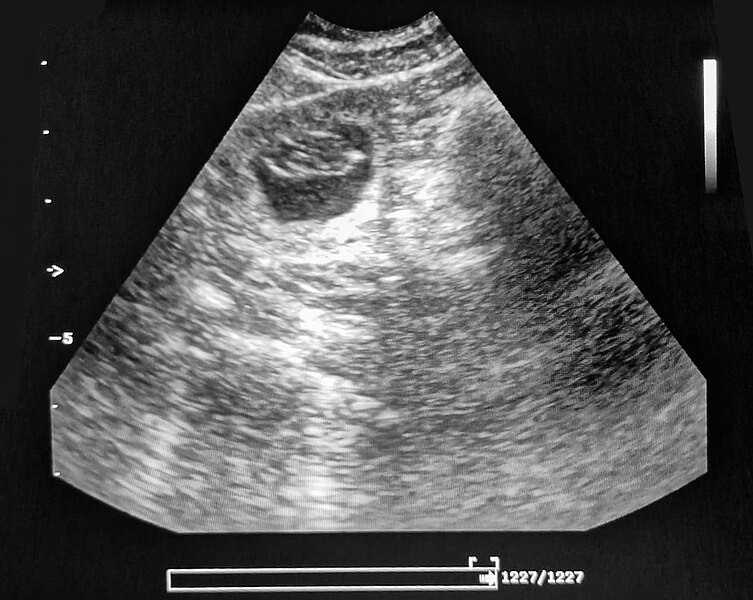

Wir waren beim Ultraschall

Zilly hat aufgenommen!